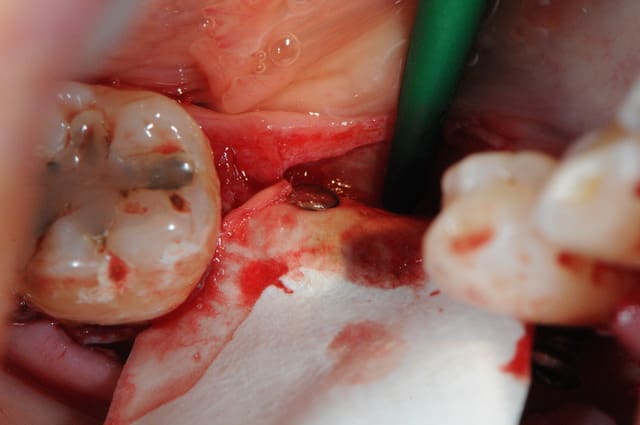

CAS 1

demande de restauration avec implant, mais, ne veut pas entendre parler de greffes et greffons.

la ROG lui semble plus "naturel".

1-2-3 situation de départ

4 après ouverture